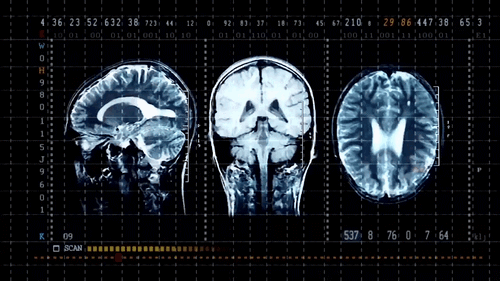

Faster Reporting Breakthrough with end-to-end AI Workflow

Natoe AI Copilot streamlines radiology workflows by combining AI-driven image analysis with intelligent case management, enabling faster, more accurate report generation within a single, unified platform.

Unified Platform for All Modalities

Copilot brings AI radiology capabilities to all imaging modalities, ensuring consistent and efficient analysis.